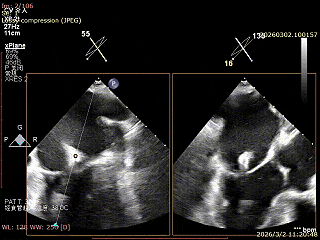

患者为房间隔缺损术后合并功能性二尖瓣反流(FMR),病变位于二尖瓣2区偏3区,因既往ASD修补史(可降解房间隔缺损封堵器),致房间隔穿刺区域存在瘢痕粘连、穿刺难度增加,于靠下靠后位置穿刺,避开房间隔缺损封堵伞,其余病变解剖结构相对简单;术前制定手术策略,拟使用1把XTR行二尖瓣修复,术中克服瘢痕粘连难点成功完成房间隔穿刺,穿刺点距二尖瓣瓣环平面3.1cm,将XTR‑CDS送入左心房,通过”A”旋钮旋转180度借高度,LVOT切面夹子严重Huge,使用”+”旋钮一键消除Huge,通过操控“M”旋钮将二尖瓣夹精准定位于2区正上方,完成弹道测试及Orientation调整后,于2区将夹子送入左心室,顺利捕捞并夹持瓣叶后缓慢闭合夹臂;TEE检查示二尖瓣反流充分降低至微量,二尖瓣双孔组织桥稳定,跨瓣压差2mmHg,肺静脉逆流明显改善,手术安全顺利结束。

可降解房间隔缺损封堵器

选择靠下靠后穿刺位点,避开房间隔缺损封堵器,避免器械损伤

房间隔成功穿刺,穿刺位点距二尖瓣瓣环平面高度3.1cm,可使用高度不足